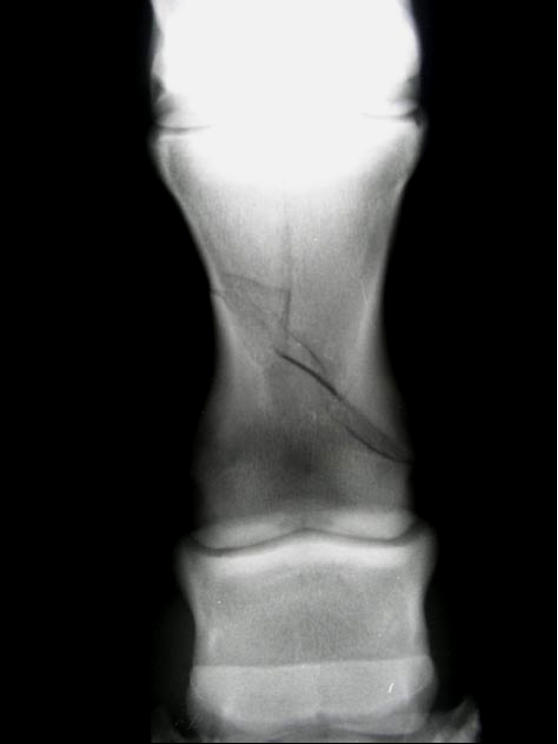

retained cartilaginous core

2 parallel lines with Lucent in the middle going towards the ulna